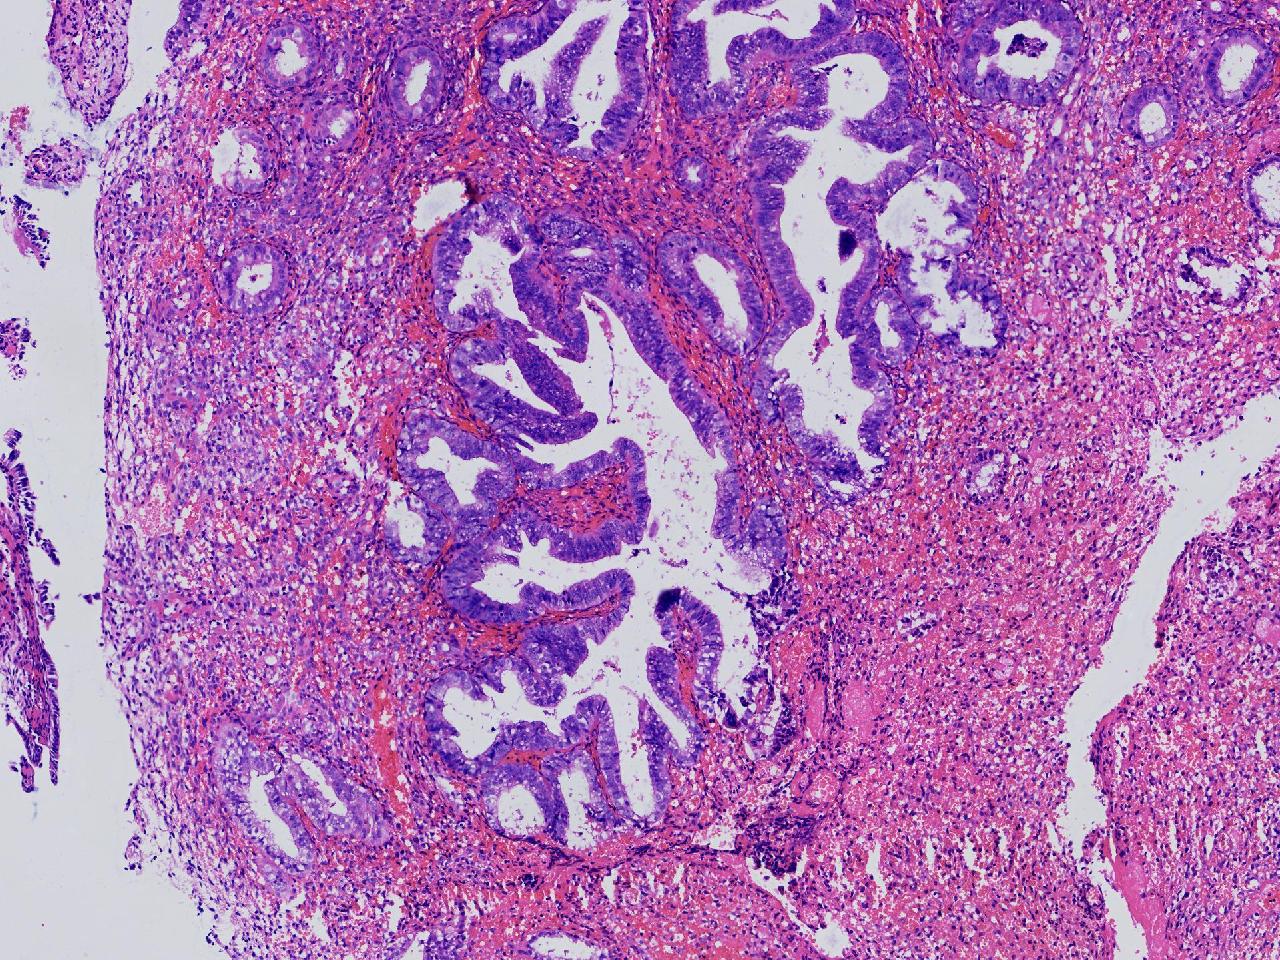

请教诊断.有没有非典?

女,50岁,彩超示:内膜厚1.3cm。

子宫内膜

灰粉色不整形软组织多块,2X2X1厘米。

无非典型性子宫内膜增生

无非典。